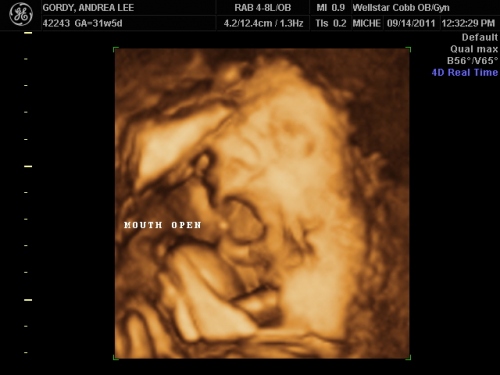

September 14, 2011- The first time we got to see his handsome face